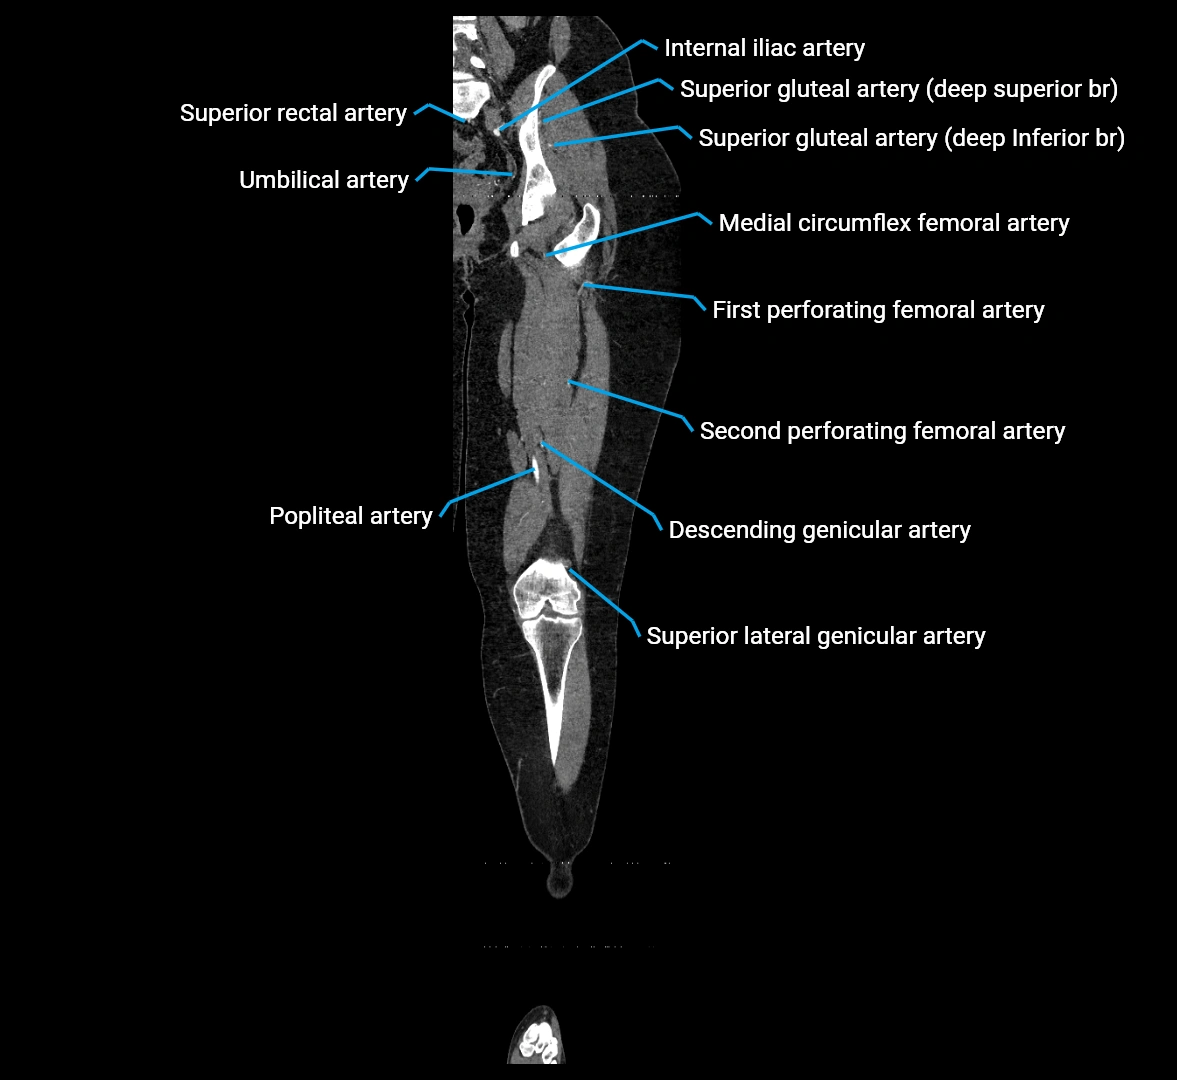

Contrast-enhanced CT (CTA):

• Gold standard for abdominal aortic imaging

• Provides excellent detail of lumen, wall, aneurysm, thrombus, and branch vessels

• Multiplanar and 3D reconstructions help in aneurysm measurement, stent graft planning, and dissection evaluation

• Detects acute rupture, traumatic injury, or occlusion with high sensitivity